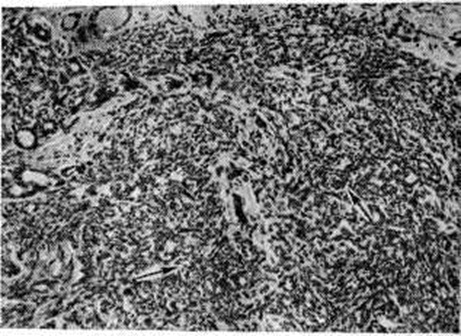

Особой разновидностью эпителиальной пролиферации при Мастопатия является склерозирующий аденоз. В так называемый цветущей фазе склерозирующего аденоза обнаруживаются очаги выраженной пролиферации эпителия ацинусов и миоэпителия (рисунок 3); образуются сплошные поля из мелких трубочек, тяжей, альвеол, лежащих в умеренно развитой строме. Постепенно процесс переходит в фиброзную фазу, при которой в полях гиалинизированной соединительной ткани сохраняются лишь отдельные, чаще всего тубулярные структуры, симулирующие в некоторых случаях гистологический картину инфильтративного рака. При пролиферативной Мастопатия выявляются также очаги фиброэпителиальной пролиферации с образованием мелких фиброаденом и цистаденопапиллом. Для цистаденопапиллом характерно формирование в протоках различной величины соединительнотканных сосочков, покрытых несколькими рядами цилиндрического или кубического эпителия (рисунок 4). В крупных протоках могут формироваться отдельные цистаденопапилломы , приобретающие самостоятельное клинические, значение.